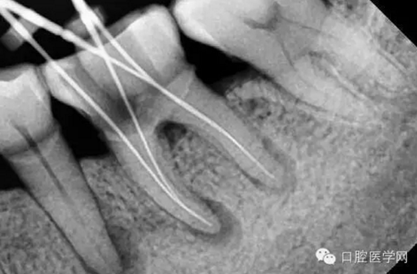

特殊情況可以插針拍片確定工作長度(一般我比較相信根測)

試尖(檢查是否恰填)

根充(從術(shù)后X光片可以看出根管充填完整,專業(yè)上叫恰充)